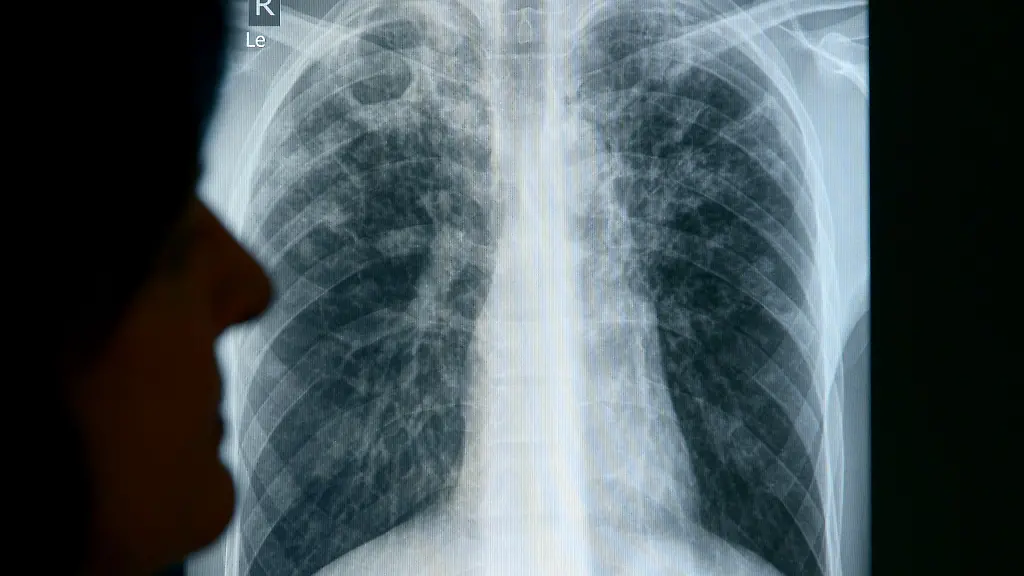

Tuberkulose ist eine Infektionskrankheit, die durch Bakterien verursacht wird und überwiegend die Lunge betrifft. Sie wird übertragen, wenn infizierte Menschen beim Husten und Niesen Erreger ausscheiden. Ohne Behandlung stirbt nach Angaben der Weltgesundheitsorganisation etwa die Hälfte der Infizierten. Mit einer vier- bis sechsmonatigen Behandlung können rund 85 Prozent der Menschen geheilt werden.